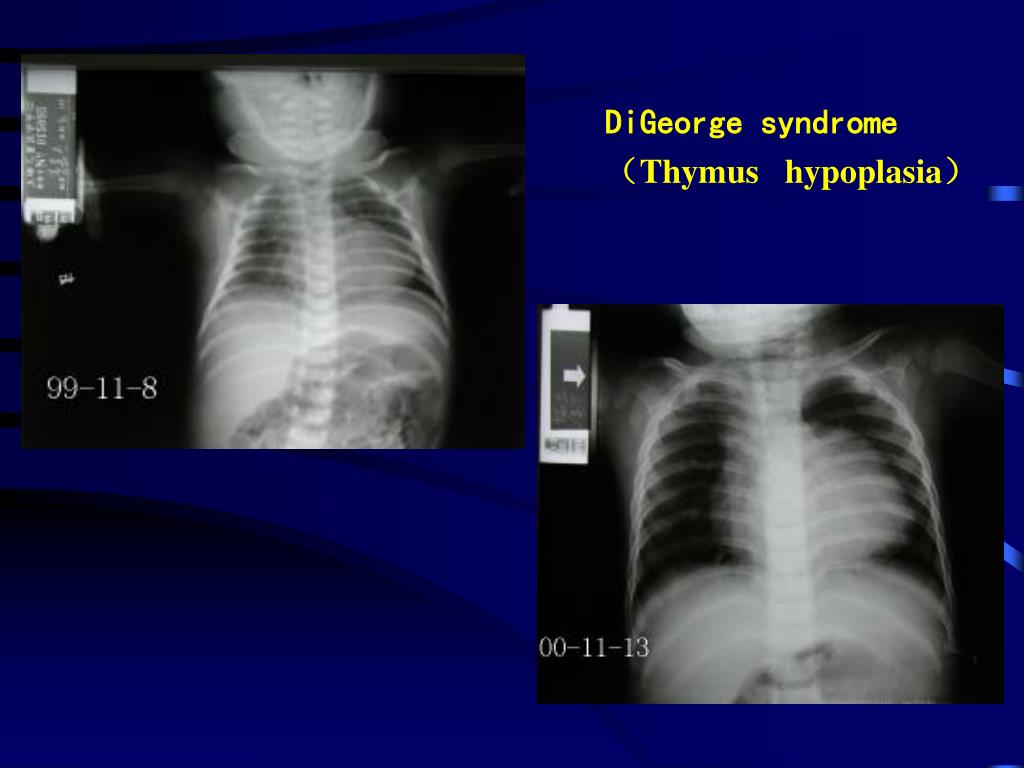

Thymic Hypoplasia Digeorge Syndrome . Digeorge syndrome is a primary immunodeficiency disorder that causes thymic and parathyroid hypoplasia or aplasia. Digeorge syndrome (dgs) is a chromosomal deletion syndrome that causes conotruncal cardiac defects, hypoplastic. Digeorge syndrome (dgs) is a genetic disorder caused by a microdeletion of chromosome 22q11.2, affecting various organs. Digeorge syndrome is a genetic disorder caused by a deletion in chromosome 22, affecting the development of the pharyngeal. By definition, complete digeorge syndrome is characterized by absence or underdevelopment (hypoplasia) of the thymus. The classic triad of features of dgs on presentation is conotruncal cardiac anomalies, hypoplastic thymus, and hypocalcemia.